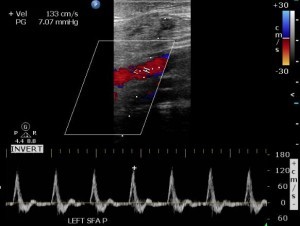

Duplex Ultrasonography

Ultrasound is great to show the flow within arteries and veins. It can help identify lesions within arteries that might be blocking flow.

In addition, ultrasound can examine the flow within veins. Ultrasound is the most common test to diagnose venous insufficiency. It is used to map areas where the valves are not functioning properly. Why would that be relevant to purple feet? Because some people have swollen purple feet. In such people, venous insufficiency is sometimes the cause.

The advantages of ultrasound are clear images, low cost, and low risk. But you have to know the limitation of the test. Unfortunately, ultrasound cannot suggest how much a finding is important. For example, it might show a narrowing in an artery. But perhaps the patient has enough redundant flow around that narrowing that makes it less important. For this reason, ultrasound should only be used if it is important to know where specific issues are. In fact, if you want to know if there is a problem at all, it is better to start with the ankle brachial index, and pulse volume recordings, as I noted above.